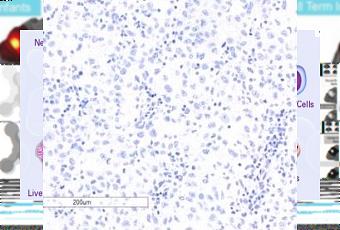

Le restaurer pour cibler la tumeur : L’équipe a d’abord cloné la protéine normale et ses versions mutées pour voir leurs effets sur les cellules de mélanome. Ils constatent que RASA2 régule une protéine clé dans la cellule, appelée RAS, un oncogène majeur qui contribue à la croissance incontrôlée des cellules. Lorsqu’ils restaurent RASA2 (visuel du bas) dans des cellules de mélanome avec version mutée (visuel du haut), ces cellules stoppent leur croissance et finalement meurent. Un résultat cohérent avec le fait que les patients atteints de mélanome avec voies RAS dysfonctionnelles ont tendance à avoir un pronostic moins favorable.